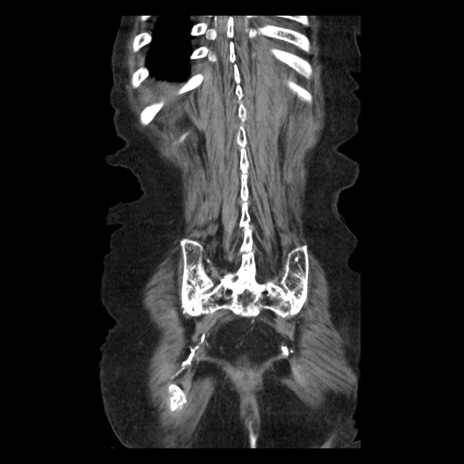

症例14(冠状断像)

【症例】 90歳代女性

【主訴】 腹痛・嘔吐

【現病歴】今朝から左側腹部痛を認めた。 経過観察していたが、嘔吐を認めたため来院。

【既往歴】 子宮癌術後

【身体所見】 意識清明、BP 127/54mmHg、P 98bpm Sp02 95%(RA)、BT 35.8°C、腹部平坦・軟腸ぜん動音聴取良好、右下腹部圧痛(+) 反跳痛なし

【データ】WBC 9800、CRP 0.46